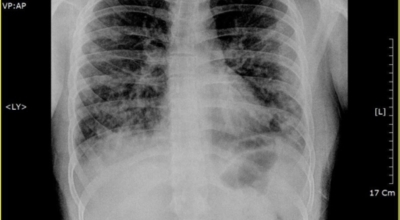

1. 금연

긴 시간의 흡연은 기도의 보호 메커니즘을 훼손시켜 기관, 기관지, 폐 간질 또는 폐에 훼손을 주어 폐 기능의 건강에 영향을 미칩니다.